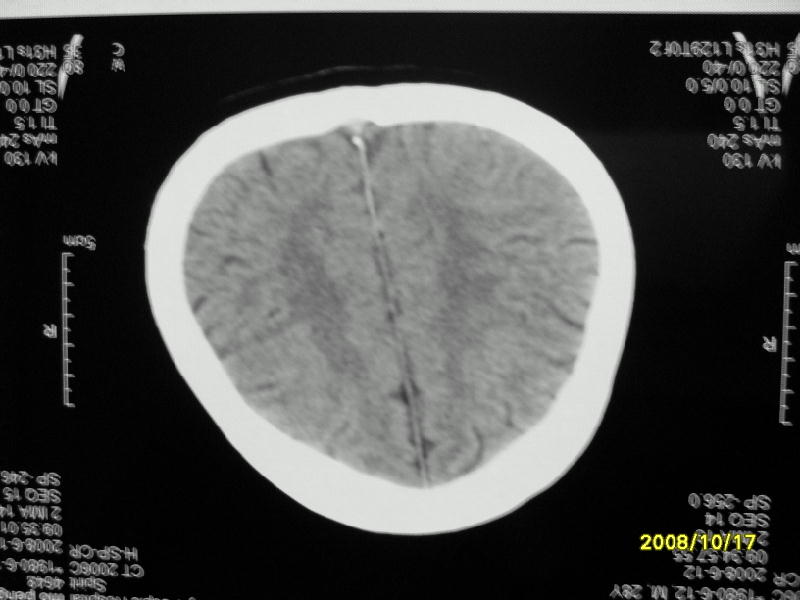

检查名称:     ct颅脑平扫           男     28岁

表现:左顶叶见斑点状致密影。边缘清,大小约0。3*1。0cm,余脑实质密度及灰白质结构示见异常。脑室系统大小,形态,密度未见异常。脑沟。脑裂。脑池未见异常密度影。中线结构无移位。

印象:左顶叶少许钙化灶

左顶叶见斑点状致密影。边缘清,大小约0。3*1。0cm,余脑实质密度及灰白质结构示见异常。脑室系统大小,形态,密度未见异常。脑沟。脑裂。脑池未见异常密度影。中线结构无移位。

印象:左顶叶少许钙化灶。

左顶叶见斑点状致密影